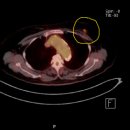

한국건강관리협회 부산센터, 고해상 64CH PET-CT가동 2013.04.25해당카페글 미리보기

한국건강관리협회 부산센터, 고해상 64CH PET-CT가동 부산 동래지하철역(1번 및 5번 출구이용) 인근에 위치한 한국건강관리협회 부산센터(원장 김태선)는 고해상 64CH PET-CT를 가동하고 있습니다. 고해상 64CH PET-CT는 암의 진단에 가장 많이 사용되며...